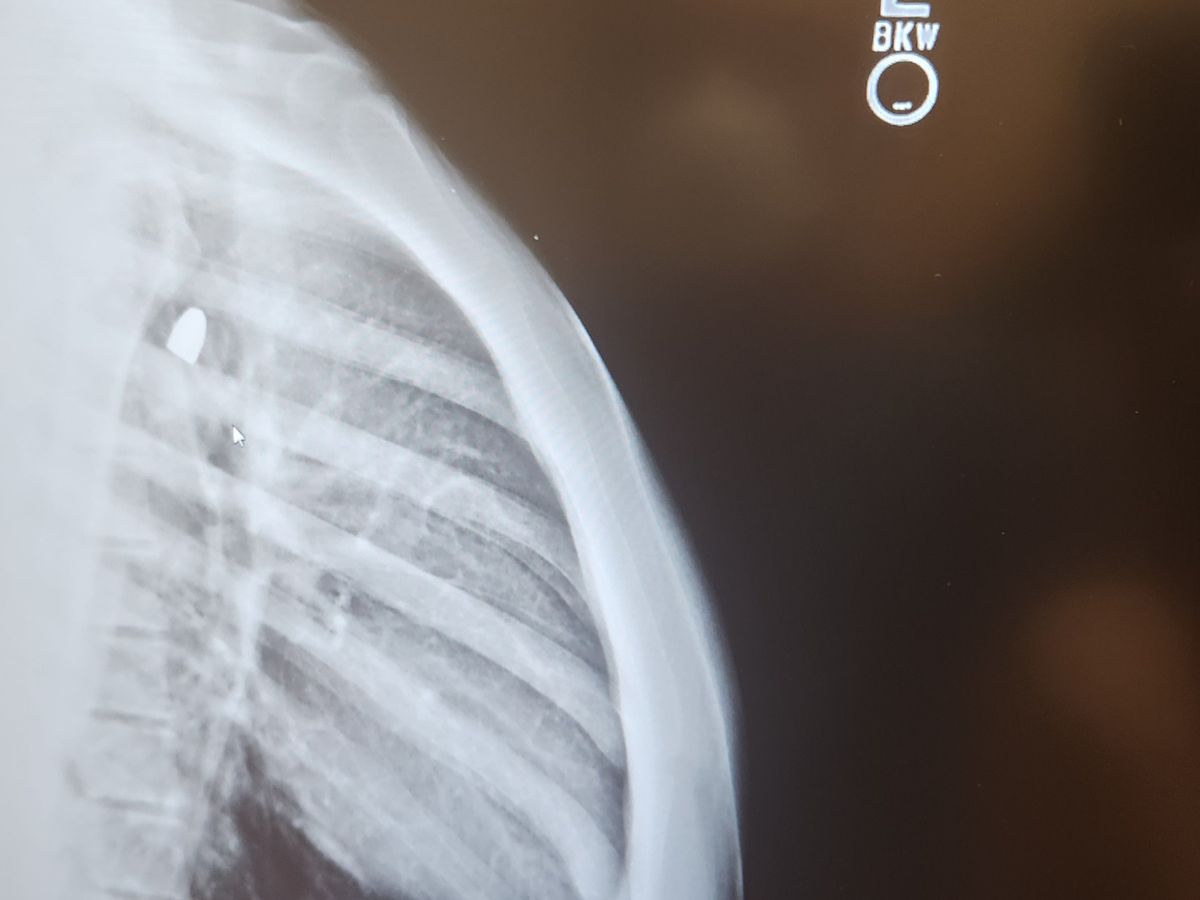

At the end or the event an angry individual opened fire on security shooting several bullets towards the event and a crowd of people. My son and one other individual where hit by these bullets. Nate who is only 17 was shot in the center of his chest and the bullet traveled about 12 inches through his body stopping in his shoulder. The bullet struck a necklace my son had on that carried my fathers ashes and went to the left. It is by the grace of god that it missed not only his heart as well other vital parts. The bullet is now sitting in his shoulder and is causing him a lot of discomfort. This has left him without the ability to do normal things like getting dressed without pain. Nate will have to have another surgery to remove to bullet when his body heals a little which will leave him down for even longer. He is no longer able to work detailing cars or even do basic thing like sweep his room.